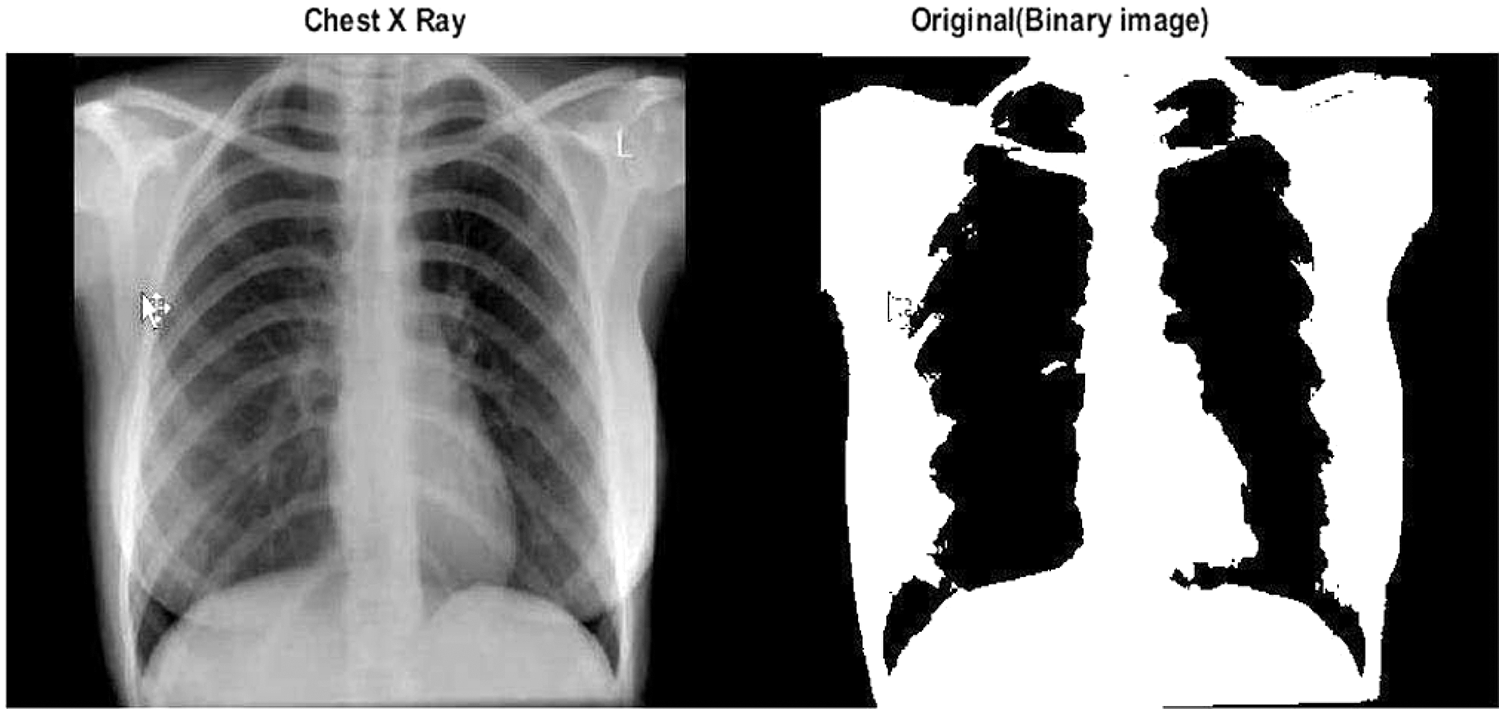

Figs. 10 and 11 show two typical chest X-ray images, one from a health subject and another from a COVID-19 patient with ARDS.

Figure 11: A chest X-ray of a healthy subject and corresponding binary image in